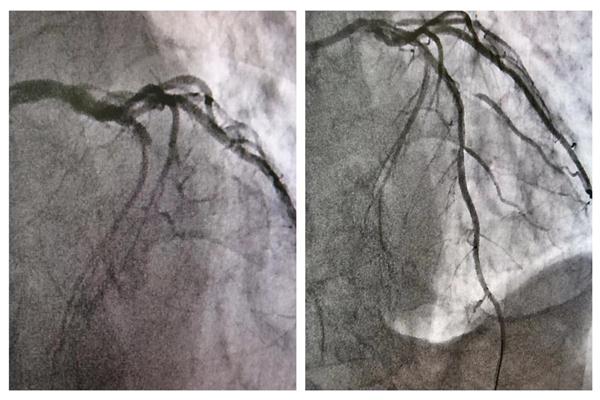

17:22患者抵达导管室行急诊冠脉造影+介入治疗,术中造影显示,犯罪血管为“前降支7段近端”呈100%闭塞,患者病情危重,没有一刻停留和犹豫,介入团队在尹哲主任的带领下紧张有序、团结协作、快速处置,17:50导丝通过闭塞段,血流恢复,行药物球囊扩张病变处,无夹层及血栓形成,手术顺利结束。术后患者胸痛消失,心率血压平稳,目前,在医师指导下,患者已能下床适度活动,再无胸痛症状反复,生命体征正常。

(术前和术后血管造影变化)